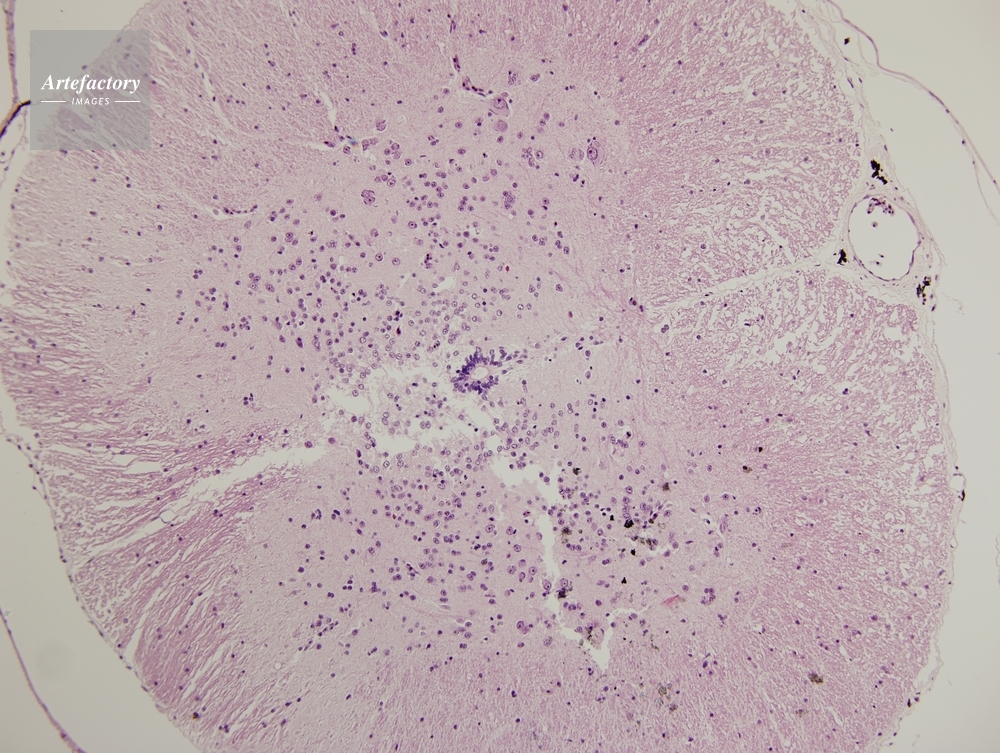

| 作品タイトル | ウシガエル,脊髄 | モデルリリース | なし | |

| 作家 | OLYMPUS CORPORATION Technolab | プロパティリリース | なし | |